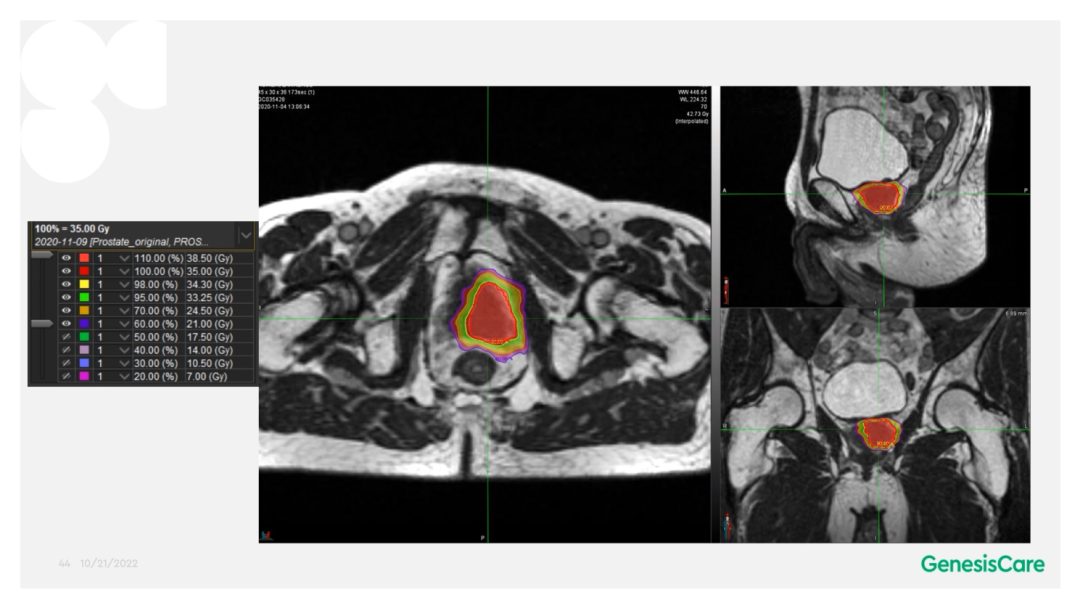

Dr. CamilleriÌåÏÖ£¬£¬£¬£¬£¬£¬£¬ËûÃÇÔÚ×öÔÚÏß×Ô˳Ӧ·ÅÁƵÄʱ¼ä£¬£¬£¬£¬£¬£¬£¬ÎªÁËÌá¸ßËÙÂÊ£¬£¬£¬£¬£¬£¬£¬½ö¶Ô°ÐÇøÍâ·Å3cmÒÔÄÚµÄΣ¼°Æ÷¹ÙµÄת±ä¾ÙÐÐ×Ô˳Ӧµ÷½â»òÖØÐ¹´»ÂÖÀª£¬£¬£¬£¬£¬£¬£¬¼ûFigure 13¡£¡£¡£¡£¡£¡£ÕâÑù¿ÉÒÔËõ¶ÌÂÖÀª¹´»µÄʱ¼ä¡£¡£¡£¡£¡£¡£¹ØÓÚ·ÅÁÆÍýÏ룬£¬£¬£¬£¬£¬£¬Ê¹µÃ95%µÄ°ÐÇøÌå»ý½ÓÊܵ½100%µÄ´¦·½¼ÁÁ¿ÁýÕÖ£¬£¬£¬£¬£¬£¬£¬²¢½«×î´ó¼ÁÁ¿ÏÞÖÆÎª2%µÄ°ÐÇøÌå»ý²»Áè¼Ý´¦·½¼ÁÁ¿µÄ110%£¬£¬£¬£¬£¬£¬£¬ÕâÑù¾ÍÄܰü¹ÜÔÚͼÏñÉϺÜÄÑÏÔʾµÄÄòµÀ²»»á³¬Á¿£¬£¬£¬£¬£¬£¬£¬¼ûFigure 14¡£¡£¡£¡£¡£¡£ÁíÍ⣬£¬£¬£¬£¬£¬£¬ÔÚÖÆ×÷·ÅÁÆÍýÏëʱ£¬£¬£¬£¬£¬£¬£¬½«PTV·ÖΪPTV LOWºÍPTV High£¬£¬£¬£¬£¬£¬£¬PTVºÍΣ¼°Æ÷¹ÙÖØµþµÄ²¿·ÖΪPTV LOW£¬£¬£¬£¬£¬£¬£¬½«PTV LOWµÄ¼ÁÁ¿Ä¿µÄÉ趨ÔÚΣ¼°Æ÷¹ÙµÄÄÍÊܼÁÁ¿ÒÔÏ£¬£¬£¬£¬£¬£¬£¬ÕâÑù¾ÍÄܰü¹ÜΣ¼°Æ÷¹Ù²»³¬Á¿£¬£¬£¬£¬£¬£¬£¬¼ûFigure 15¡£¡£¡£¡£¡£¡£

Dr. CamilleriÏÈÈÝÁËһλ72Ë꣬£¬£¬£¬£¬£¬£¬ÔÚ2006Äê½ÓÊÜÁË55Gy/20F·ÅÁƺ󸴷¢µÄǰÏßÏÙ°©»¼Õß¡£¡£¡£¡£¡£¡£ÆäʱËüµÄPSAΪ28£¬£¬£¬£¬£¬£¬£¬¾Ö²¿ÍíÆÚ£¬£¬£¬£¬£¬£¬£¬ÆÚ±ðΪT3aN0M0¡£¡£¡£¡£¡£¡£PET-CTÏÔʾǰÏßÏÙ×óºó²¿¾Ö²¿¸ß´úл£¬£¬£¬£¬£¬£¬£¬»î¼ìҲ֤ʵÁËÕâÒ»µã£¬£¬£¬£¬£¬£¬£¬²¢ÇÒ»î¼ìЧ¹ûÅú×¢Ö×ÁöÇÖÈë×ó²à¾«ÄÒÏٵײ¿¡£¡£¡£¡£¡£¡£½«ÆäMRIdian MRIͼÏñºÍPET-CTͼÏñÈںϺ󣬣¬£¬£¬£¬£¬£¬ÔÙÆ¾Ö¤»î¼ìЧ¹ûÈ·¶¨°ÐÇø£¬£¬£¬£¬£¬£¬£¬¼ûFigure 20-22£¬£¬£¬£¬£¬£¬£¬²¢ÖÆ×÷·ÅÁÆÍýÏë¡£¡£¡£¡£¡£¡£·ÅÁƼÁÁ¿Îª35Gy/5´Î£¬£¬£¬£¬£¬£¬£¬Äý½º×è¸ôÎïºÜºÃµØ°üÀ¨ÁËÖ±³¦£¬£¬£¬£¬£¬£¬£¬¼ûFigure 23£¬£¬£¬£¬£¬£¬£¬°ÐÇøºÍΣ¼°Æ÷¹ÙÊÜÁ¿¼ûFigure 24¡£¡£¡£¡£¡£¡£»£»£»£»£»£»£»¼ÕßÓÚ2020Äê12Ô½ÓÊÜÖÎÁÆ£¬£¬£¬£¬£¬£¬£¬ËûÌåÖʺܺ㬣¬£¬£¬£¬£¬£¬ÔÚ·ÅÁÆÊ±´úºÍÖ®ºó£¬£¬£¬£¬£¬£¬£¬¼á³ÖÿÖÜÈý´Î5¹«ÀïÅܲ½£¬£¬£¬£¬£¬£¬£¬Ê¼ÖÕδ·ºÆðGUºÍGI¶¾ÐÔ¡£¡£¡£¡£¡£¡£ËûµÄPSA×îµÍֵΪ0.45£¬£¬£¬£¬£¬£¬£¬ÔÚ2022Äê5ÔµÄËæ·ÃÊý¾ÝÖУ¬£¬£¬£¬£¬£¬£¬ØºÍè¼¤ËØË®Æ½»Øµ½ÁËÕý³£µÄ33%¡£¡£¡£¡£¡£¡£ÔÚ2022Äê1ÔµķÅÁƺóPSMA PETµÄͼÏñÉÏ£¬£¬£¬£¬£¬£¬£¬Î´¼ûÖ×Áö¸ß´úл¼ûFigure 25¡£¡£¡£¡£¡£¡£